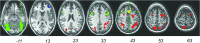

Re-entrant circuits involving communication between the frontal cortex and other brain areas have been hypothesized to be necessary for maintaining the sustained patterns of neural activity that represent information in working memory, but evidence has so far been indirect. If working memory maintenance indeed depends on such temporally precise and robust long-distance communication, then performance on a delayed recognition task should be highly dependent on the microstructural integrity of white-matter tracts connecting sensory areas with prefrontal cortex. This study explored the effect of variations in white-matter microstructure on working memory performance in two separate groups of participants: patients with multiple sclerosis and age- and sex-matched healthy adults. Functional magnetic resonance imaging was performed to reveal cortical regions involved in spatial and object working memory, which, in turn, were used to define specific frontal to extrastriate white-matter tracts of interest via diffusion tensor tractography. After factoring out variance due to age and the microstructure of a control tract (the corticospinal tract), the number of errors produced in the object working memory task was specifically related to the microstructure of the inferior frontal-occipital fasciculus. This result held for both groups, independently, providing a within-study replication with two different types of white-matter structural variability: multiple sclerosis-related damage and normal variation. The results demonstrate the importance of interactions between specific regions of the prefrontal cortex and sensory cortices for a nonspatial working memory task that preferentially activates those regions.